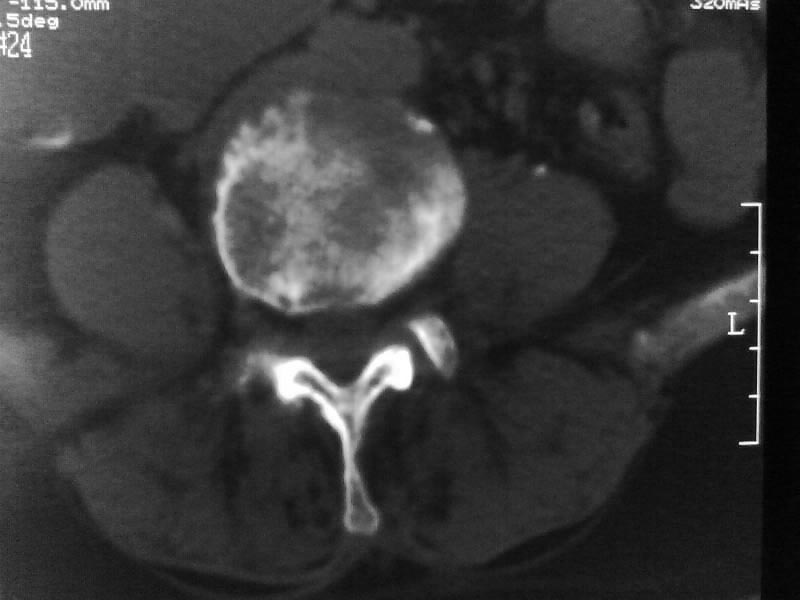

定位相示l2呈楔形改变(ct示陈旧性骨折改变,图像未传),l4.5椎体融合,以下是l4.5ct平扫.请各位看看,

考虑结核(有破坏、硬化及死骨)。

1、三四椎体结核,2、水平骶椎。

1、l1压缩性骨折(陈旧性)。

2、l3、4椎体结核。

就是腰1压缩性骨折,腰3\\4椎体结核(融合),水平骶椎.

支持 l1椎体陈旧性压缩性骨折;l3、4椎体结核(融合);水平骶椎。